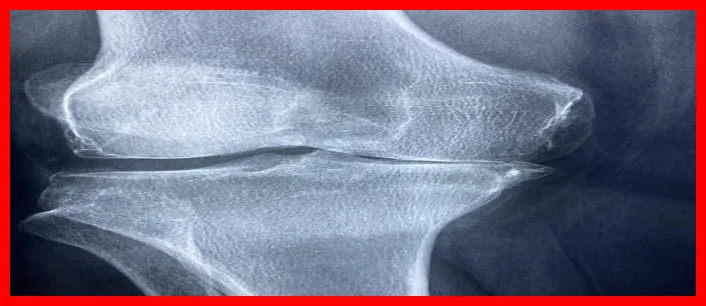

류마티스 관절염은 주로 관절에 영향을 미치는 만성 염증성 질환입니다. 이 질환은 면역 시스템이 신체의 정상 세포를 공격함으로써 발생하며, 보통 관절의 붓기와 통증을 유발합니다.

면역 체계가 자가 면역 반응을 일으키는 과정에서, 여러 관절에 염증이 발생하게 되어 통증을 경험하게 되는 것이죠. 이 질환은 전신에 걸쳐 영향을 미칠 수 있으며, 조기 발견이 중요합니다.

- 관절 통증: 주로 손가락, 손목, 무릎 등에서 통증이 발생합니다.

- 관절의 부기: 염증으로 인해 관절이 붓고 열이 발생할 수 있습니다.